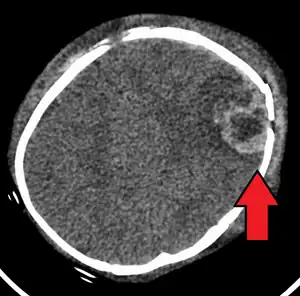

| An intraparenchymal bleed with overlying skull fracture from shaken baby syndrome | |

Diagnosis can be difficult as symptoms may be nonspecific.[1] A CT scan of the head is typically recommended if a concern is present.[1] It is unclear how useful subdural haematoma, retinal hemorrhages, and encephalopathy are alone at making the diagnosis.[25]

A skull fracture from abusive head trauma in an infant